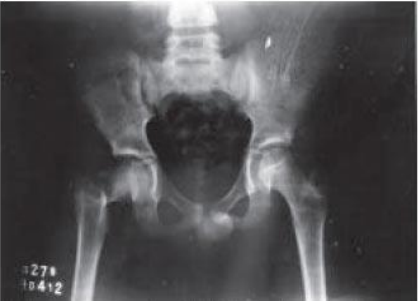

Com base na classificação de Delbet, analise a radiografia, abaixo:

Com base na radiografia, podemos afirmar que se trata de: